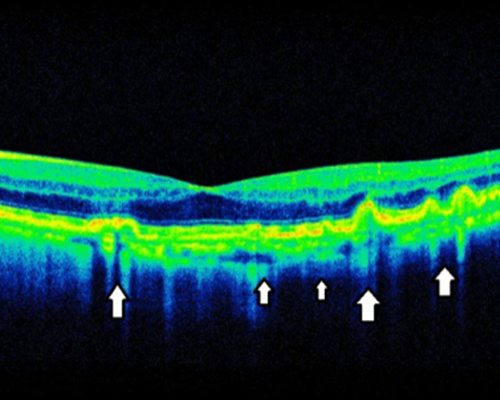

눈에 영양을 공급하는 모세혈관이 미세하게 파열되어 황반을 받쳐주는 세포 조직이 약해지고, 황반 부분이 이탈되어 나타나는 시력저하 질환입니다

황반부에 생긴 망막하액과 망막색소상피박리

자주 재발될 수 있고, 만성화 되는 경우 황반 변성으로 진행할 수 있으므로 예방이 매우 중요합니다.